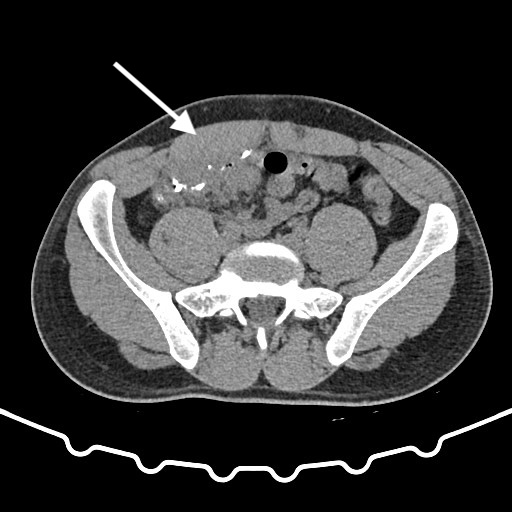

Three years after the appendectomy, the patient returned to the emergency department due to periumbilical pain and erythema that had persisted for three months. On further questioning the patient also reported intermittent diarrhea for one week, with no accompanying vomit or fever. During the physical examination, erythema and pain upon palpation of the umbilicus were observed. The blood tests showed no significant changes. Imaging with a CT scan and fistulogram through the umbilical granuloma allowed for the identification of a fistulous tract to a pericecal collection (figure 1-3). The patient was admitted and started on empiric antibiotic therapy with piperacillin and tazobactam.

Fig. 1-2: CT scan with fistulogram through the umbilical granuloma showing the fistulous tract to the cecum (white arrow) - axial view.